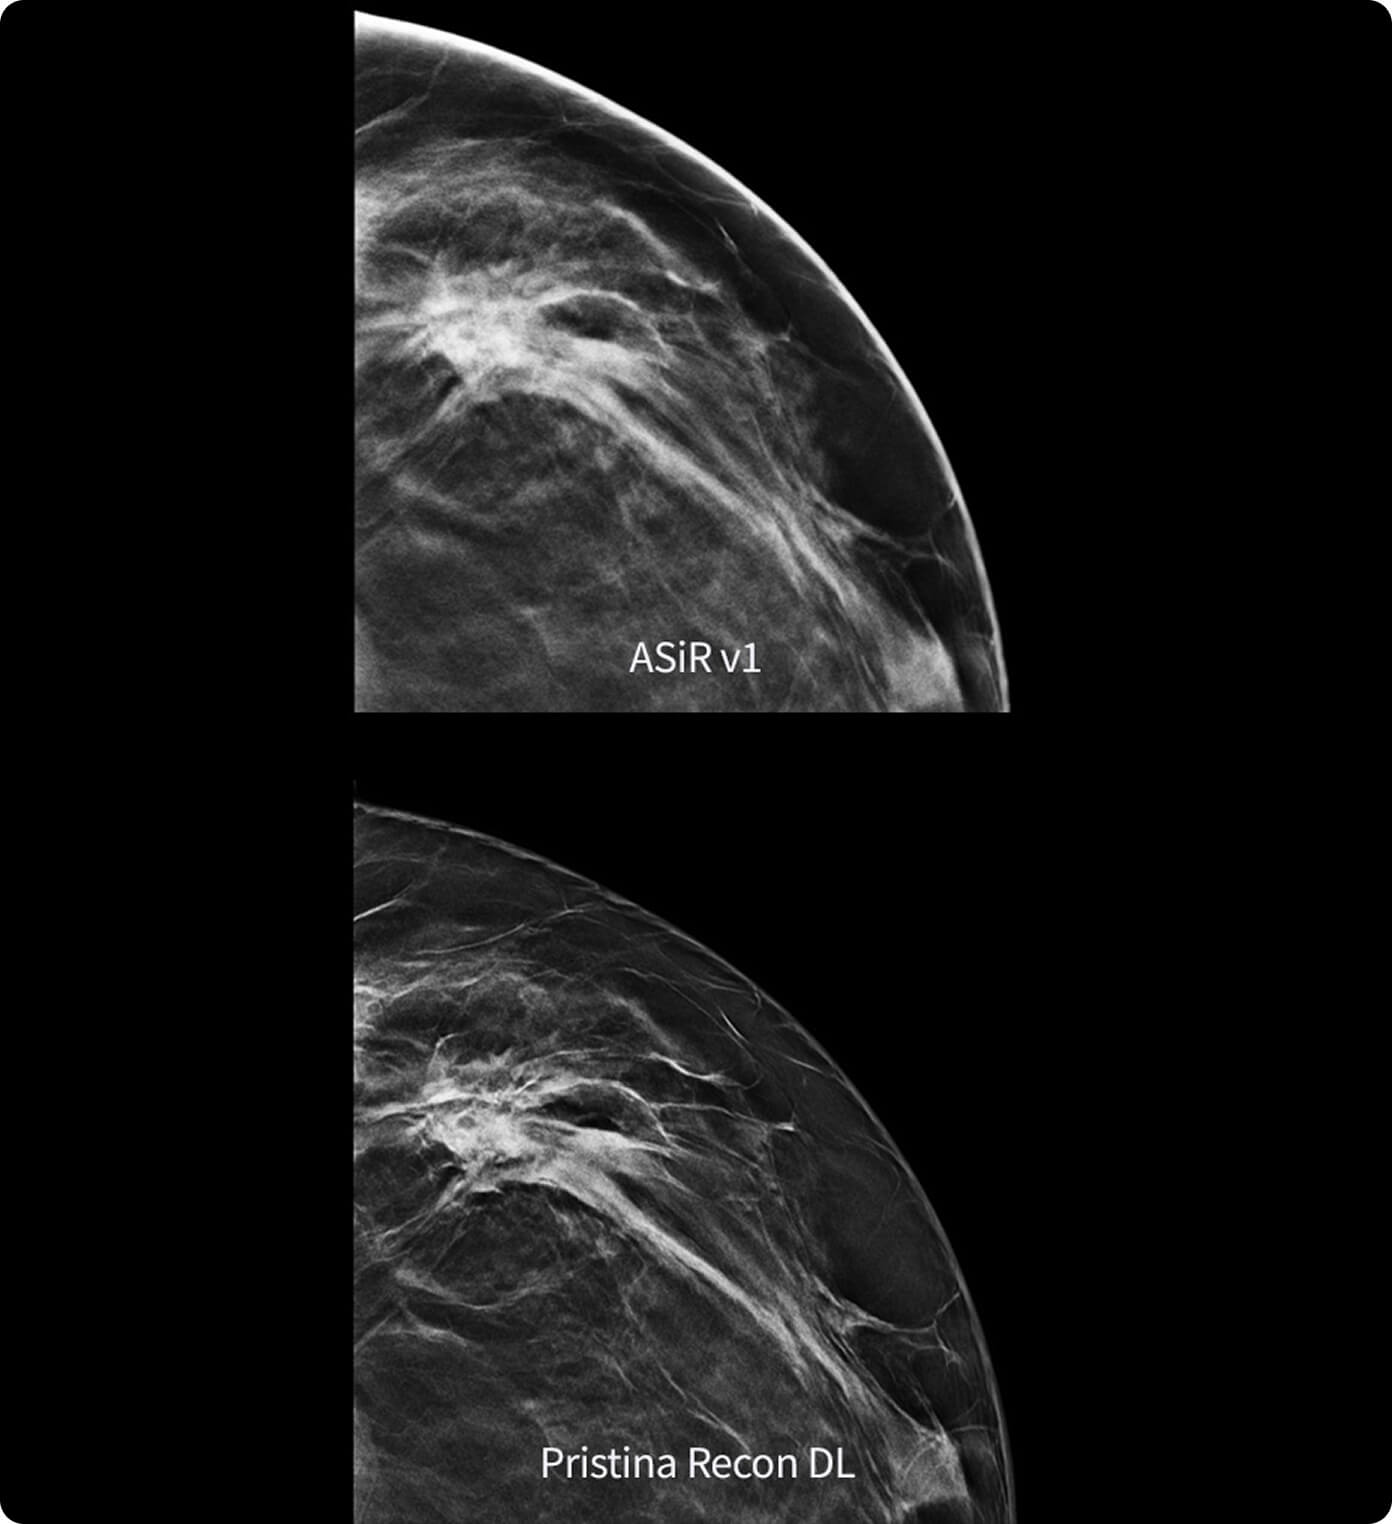

La prima soluzione per la gestione del movimento respiratorio che non include un dispositivo di gating. Monitora attivamente il movimento respiratorio in background di ogni procedura PET/TC. Quando rileva un'anomalia, modifica automaticamente la scansione e integra ciò che apprende nell'immagine finale in tempo reale.